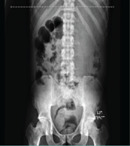

There are a few reported cases of bone metastasis from adenocarcinoma of the appendix and there is none from Africa. We report this rare case of a 30-year-old man who presented with low back pain following a trivial fall and who subsequently developed generalized peritonitis for which he underwent laparotomy. The histology of the appendix and the mesentery confirmed adenocarcinoma of the appendix with metastasis to the mesenteric lymph nodes while an MRI scan confirmed spine metastasis. Carcinoma of the appendix, should, therefore, be considered as a differential diagnosis in spine metastasis of unknown origin especially with coexisting abdominal symptoms.

Abstract Image